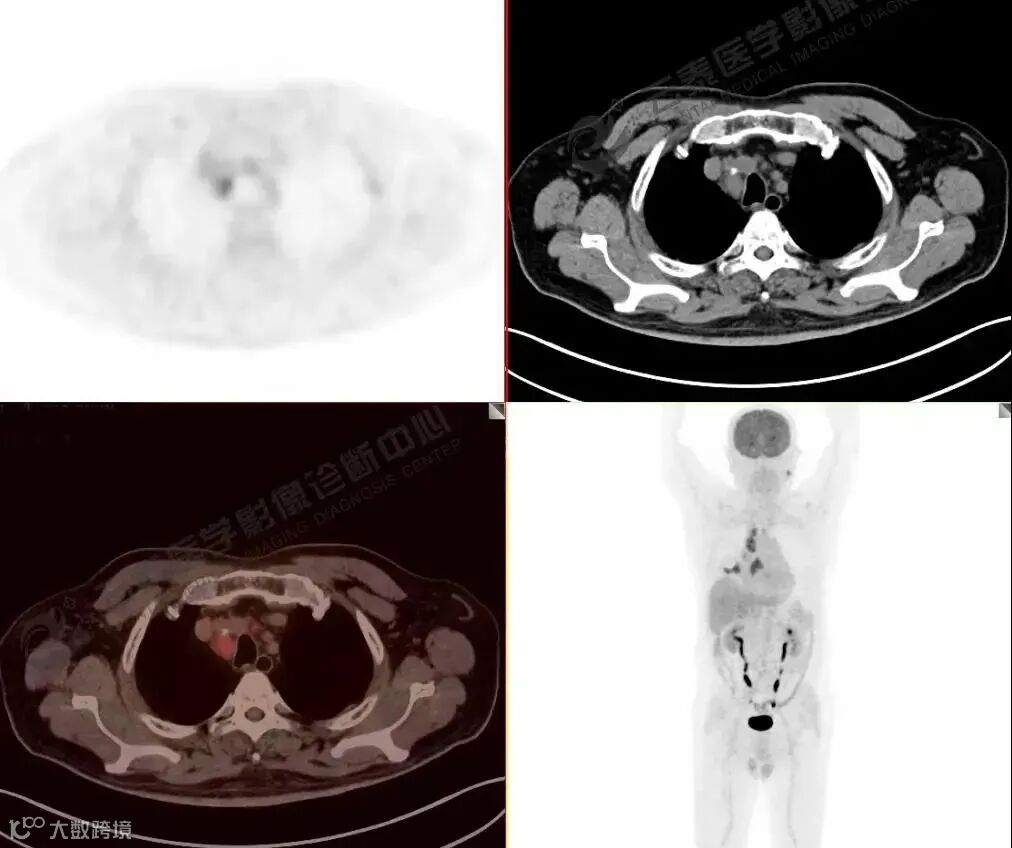

PET-CT等于PET+CT,包含PET(功能分子影像)与CT(解剖影像)的最优化组合;即同时具有PET和CT的功能,但它绝不是二者功能的简单叠加,因为PET与CT优势互补,“1+1>2”。

PET-CT除了具备PET和CT各自的功能外,其独有的融合图像,将PET图像与CT图像融合, 可以同时反映病灶的代谢,可以早期诊断疾病的同时,明显提高诊断的准确性。

PET-CT在肿瘤方面的应用占其临床应用的90%以上,最常用的显像剂为18F标记的FDG(18F-FDG)。PET-CT的主要适应症概括为:

对肿瘤高危人群,早期发现或排除肿瘤;

对肿瘤标志物不明原因升高,寻找肿瘤病灶所在;

对已发现可疑病变者,鉴别良、恶性;

对可疑肿瘤患者,指导选择最有价值的活检部位;

对已发现肿瘤转移者,寻找原发灶。

对恶性肿瘤患者,进行更准确分期;

肿瘤恶性程度分级和预后判断;

指导放疗计划靶区的设定。

肿瘤肿瘤术后及放化疗后疗效的评估;

肿瘤残存病灶与坏死、纤维化组织的鉴别;

肿瘤治疗后寻找残存、复发或转移病灶;

肿瘤复发的监测。

神经精神系统、心血管系统等方面

对癫痫灶准确定位及抑郁症、帕金森氏病、老年性痴呆等疾病的研究;

心肌活力测定等。